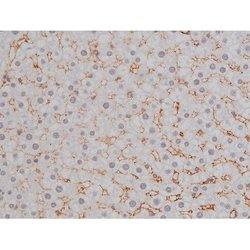

Invitrogen™ Phospho-NPM1 (Thr199) Polyclonal Antibody

Antibody detects endogenous levels of Nucleophosmin only when phosphorylated at Threonine 199.

| Applications | Immunohistochemistry (Paraffin), Western Blot, Immunocytochemistry |